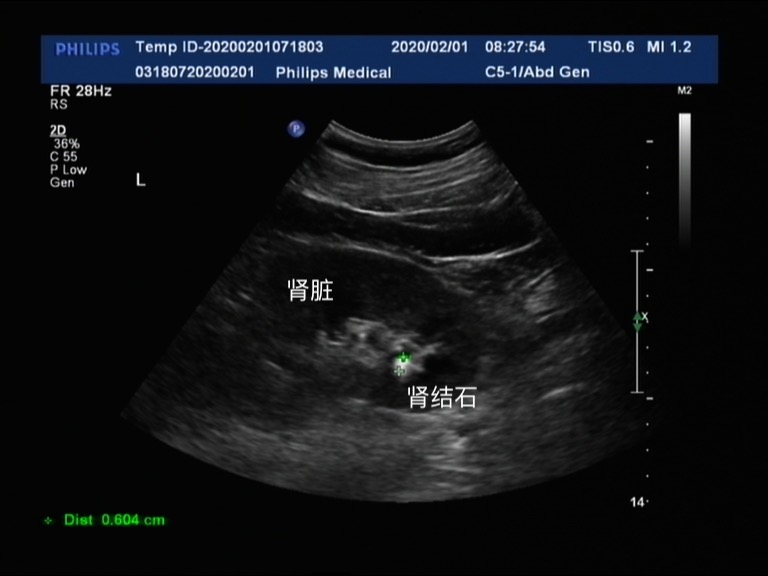

比较小的肾结石,体积在0.6cm左右的时候,当它形成后,会脱落掉到我们的输尿管里。这个时候它就不称为肾结石了,而是换了一个名称叫做输尿管结石!